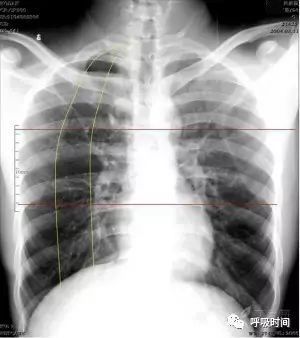

一般讲,下颈部、双侧肋膈角纳入片内;两侧胸廓对称,黑化度、对比度适中,胸 1-4 椎体隐约可见(图 1,现在的数字化摄影如 CR、DR,往往曝光过度,所以,有时会隐约可见脊柱影)。无佩饰衣物等干扰。

图 1 为胸部正侧位片

双肺(血管)纹理清晰(至胸膜下 3 cm / 限于肺野中内带);肺门结构不大、清晰。心影大小形态无异常,纵隔无偏移。双侧肋膈角锐利,胸廓对称